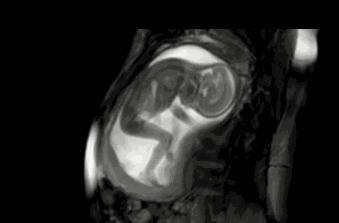

母爱的本能,会从怀孕开始。得知自己怀孕的消息后,每位女性会自动进入母亲的角色。

尤其是头胎怀孕的妈妈,会对肚子里的胎儿保持特别的关注,唯恐因自己一丁点的“失误”伤害到他,毕竟怀孕的风险性太高了。

怀孕的过程是辛苦的,除了孕妈身体会出现各种不适之外,她们有时候也会被胎儿突然的举动吓得不知所措。

胎儿在孕妈的体内,通过脐带从母体内过的营养和氧气,以获得发育和成长。差不多到了28周的时候,他们已经具备基本的吞咽能力。

“羊水是胎儿的生活环境,为了锻炼自己的吞咽能力,胎儿会通过吞咽羊水的方式。而当吞咽的太急的时候,就会导致“打嗝儿”情况的出现。”